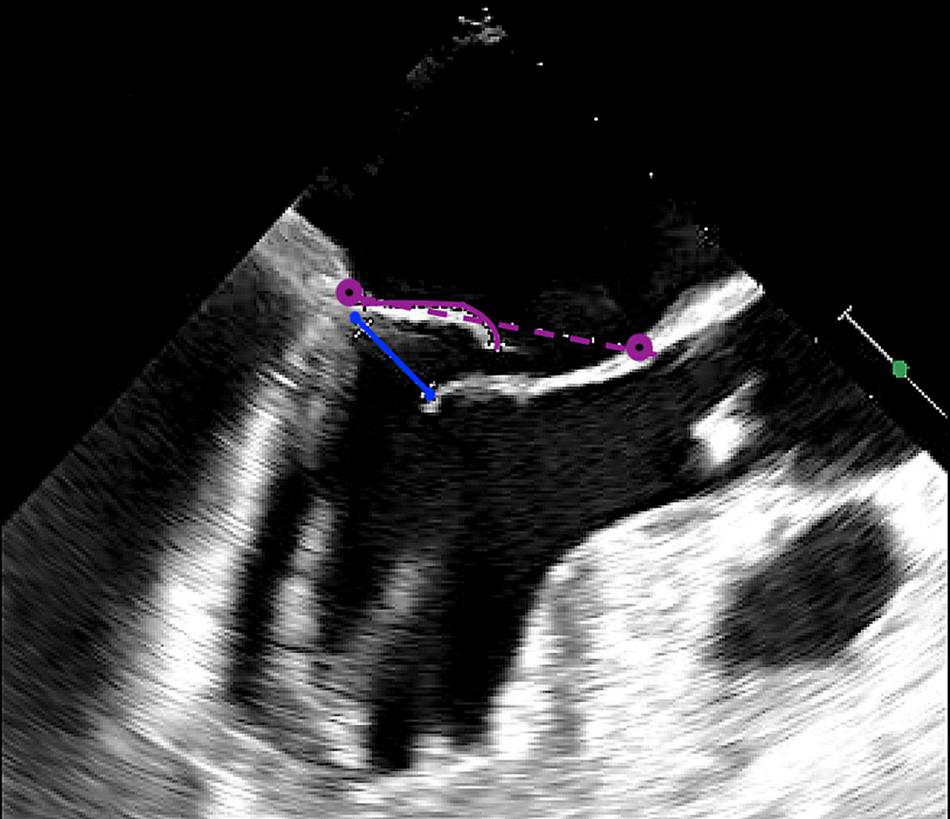

We report the selection criteria based on the current practice as applied in our center (Table 2). Patients are considered eligible for a Harpoon BHMVR procedure in case of severe DMR due to mid-segment pMVL (P2) prolapse, as determined on echocardiography. Although transthoracic echocardiography (TTE) is often used for the primary diagnosis, complementary transesophageal echocardiography (TEE) (e.g., with Philips EPIQ 7) including 3D clips is required to meticulously identify the mechanism of MR and extent of the prolapsing segment. In order to reduce MR without undue leaflet tension after cord implantation, the mitral leaflet coaptation surface needs to be sufficient. Sufficient coaptation is defined by a minimum tissue to gap ratio of 1.5:1, measuring the posterior prolapse segment length and the corresponding anteroposterior distance between the free edge of the anterior leaflet and the base of the prolapsed posterior leaflet segment (Figures 2, 3). Patients that have more extensive pMVL prolapse, with involvement of P1 and/or P3, and/or additional anterior leaflet prolapse are thus far not considered eligible for the procedure. Other major exclusion criteria are active endocarditis, left ventricular or left atrial appendage thrombus, severe mitral annular and/or leaflet calcification, mitral stenosis, functional MV disease, previous MV replacement surgery and a fragile or thinning apex. Patients with significant aortic or tricuspid stenosis or regurgitation requiring concomitant cardiac surgery are also not seen as optimal candidates for BHMVR with the Harpoon system.

FIGURE 3

Intraoperative long-axis TEE view showing part of the left atrium, the left ventricle and the left ventricular outflow tract, before repair with the HARPOON device. The measurement of the tissue/gap-ratio is demonstrated. Tissue-length, 1.98 cm; gap-length, 1.14 cm. Tissue/gap-ratio = 1.98/1.14 = 1.74. The anteroposterior diameter is 3.76 cm.